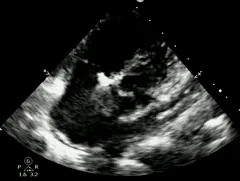

首次术后超声复查

TTE左室长轴显示:左室后壁心包积液(微~少量),2mm。

二次术中超声会诊

VSD(膜周部):左室面6.5mm,隔瓣下残缘5mm,基底形成5mm入口,右室面呈“瘤样”结构,出口孔2.5mm,三尖瓣隔瓣构成瘤壁的一部分。